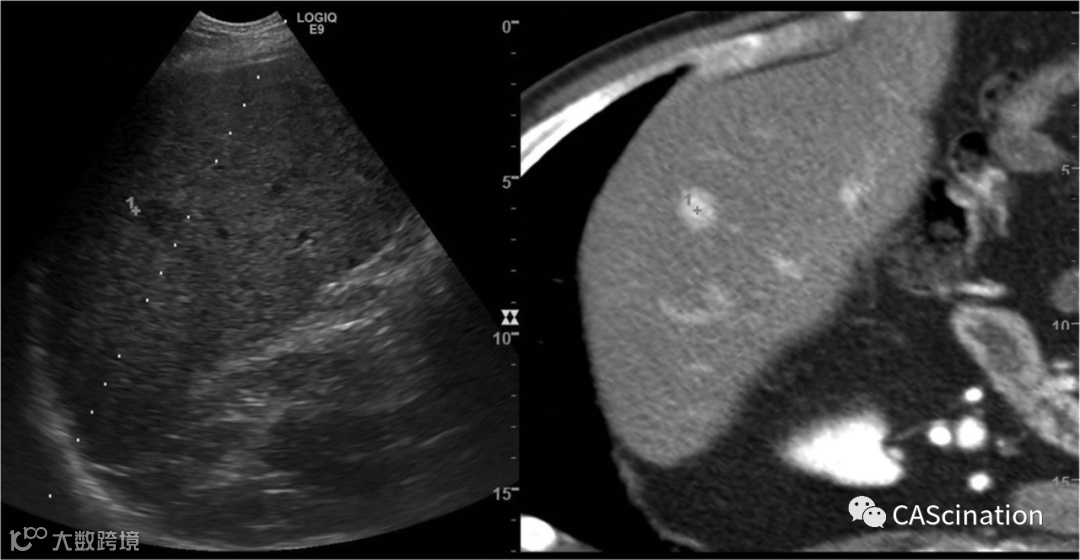

容易识别的肝血管被用于可靠的融合,因此无论肿瘤是否明显,都可用于高精度的治疗探头放置。由于融合可以确保超声肿瘤检测集中在感兴趣的区域内,因此通常甚至可以检测几乎看不见的病变,并且使用对比增强超声(CEUS)可以进一步提高准确性(图1)。

图1。肝脏肿瘤动脉负荷的ct与活体超声相结合,更容易定位。